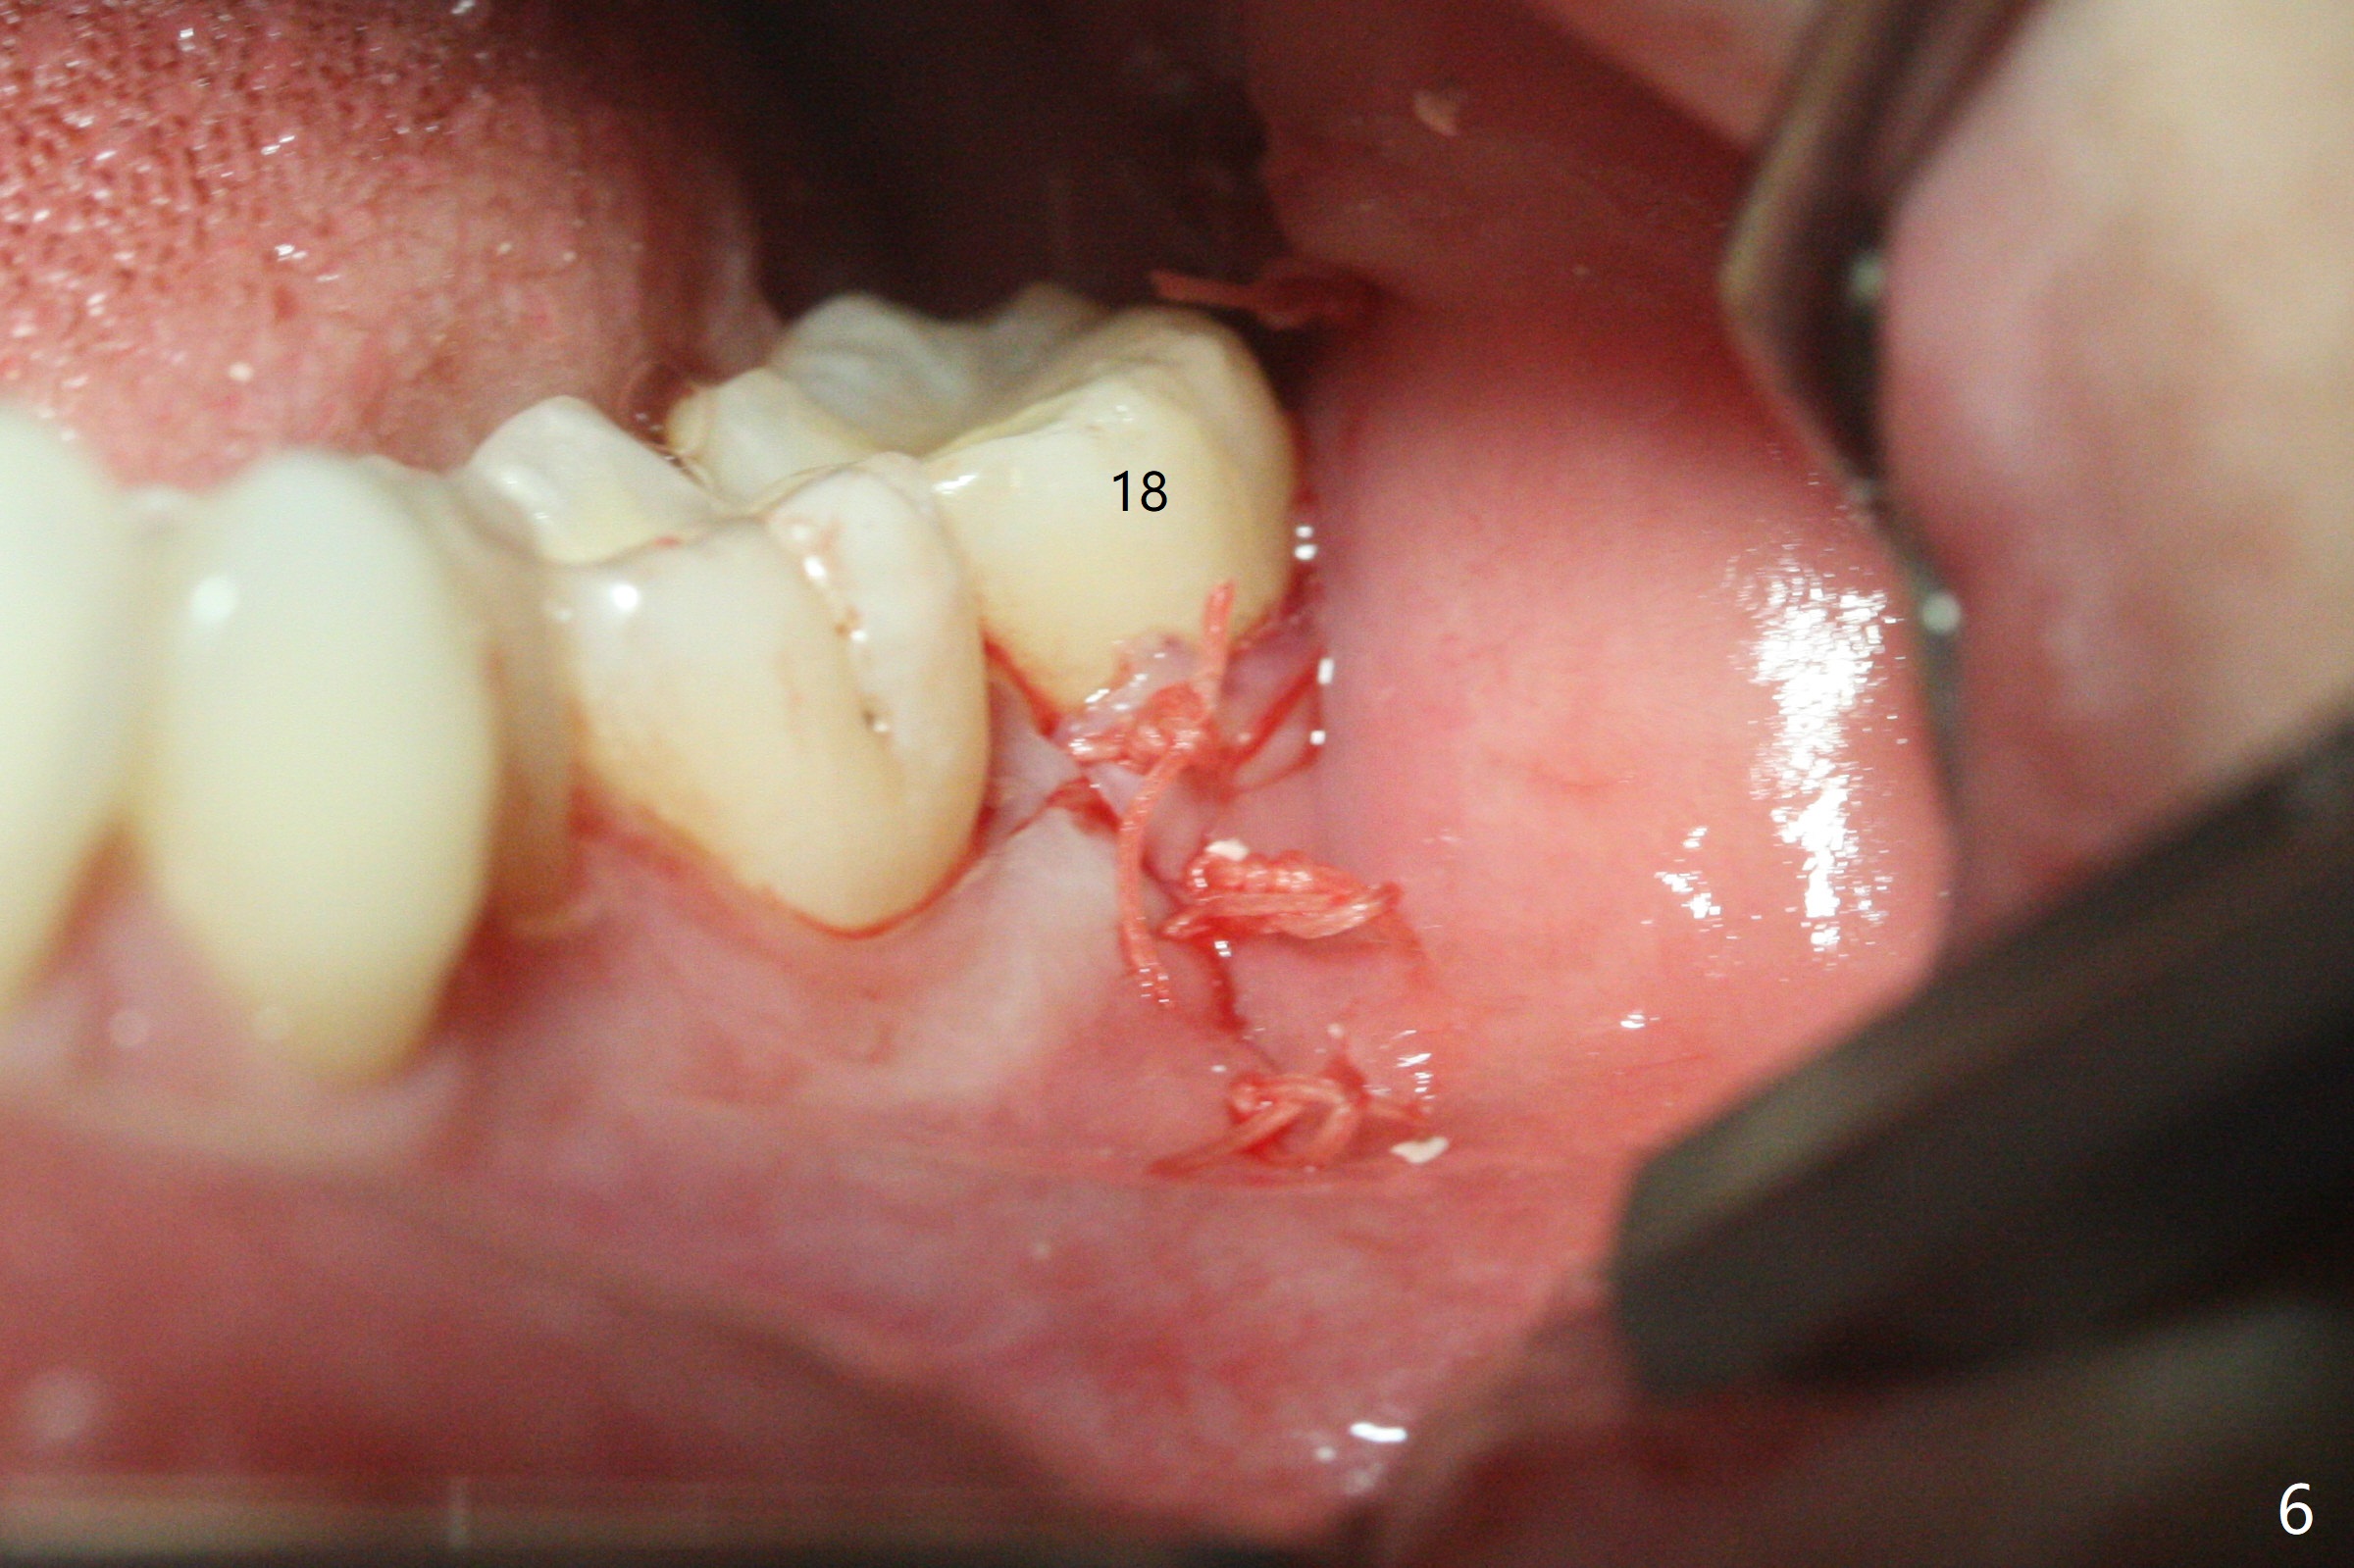

A 27-year-old woman (nervous) is going to return for #16 and 17 extraction (Fig.1). Offer sedative (Valium) if she cannot overcome fear. Take PAs for #17 and 32 to confirm Buccal Impaction, which dictates position of the accessory incision to reduce loss of bone graft in case of wound dehiscence. Place Collagen Plug (1/2 piece) in the apical portion of the sockets of the lower 3rd molars, while Augma and Osteogen Plug (1 piece) in the coronal half of #17 and 32, respectively. Place additional Collagen Plug for the remaining socket if needed before 4-0 PGA suturing as the 2nd step to decrease the chance of losing bone cement. Preop PA shows that the tooth #17 seems to be mesial (Fig.2 arrow). The accessory incision is placed mesiobuccal of the tooth #18 (Fig.4 red oblique line, Fig.6) so that it is not overlying the bony defect (Fig.4 arrowheads). Since the access to the impacted tooth is limited, small field of CT is taken (Fig.3,4), which shows the root is yet to be exposed (Fig.3 R). After tooth removal, Collagen plug is placed in the apex of the socket for hemostasis (Fig.5 C), while Bond Apatite coronal for bone regrowth (A). There is no dehiscence 11 days postop (Fig.7), although the patient complains of pain in the jaw and the temporomandibular region. The anterior portion of the external oblique ridge forms 1 year 7 months postop (Fig.8).